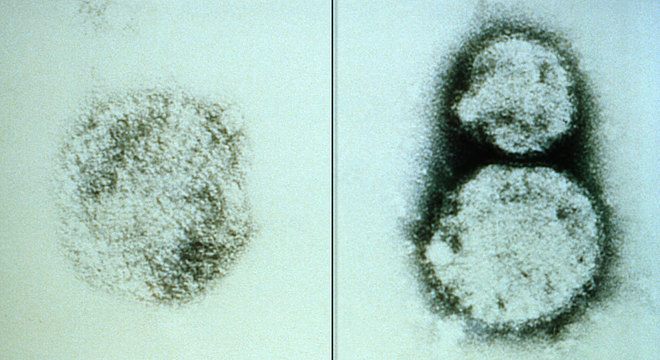

Não há tratamento específico para a hantavirose e quase quatro a cada dez pessoas morrem após a contrair a doença Getty Images / BBC NEWS BRASIL

A hantavirose é uma doença viral grave transmitida por roedores. É comum que sejam registrados casos de contágio por hantavírus a cada ano em países da América do Sul, inclusive o Brasil. Mas um surto fatal da doença no sul da Argentina tem chamado a atenção.

O mais comum é que o contágio ocorra diretamente pela inalação de partículas de urina, fezes e saliva de roedores silvestres – não pelo contato com outros humanos infectados. Por isso, os casos da doença costumam ser isolados. Diferentemente dos seres humanos, roedores, como ratos e ratazanas, podem carregar o hantavírus por toda a vida sem adoecer.